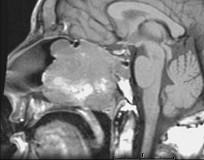

问题 15岁,男性,渐进性鼻塞1年余,MRI扫描如图所示,请选择最可能诊断()

选项 A.鼻咽部纤维血管瘤 B.鼻咽部脓肿 C.脊索瘤 D.鼻咽部囊肿 E.鼻咽癌

答案 A